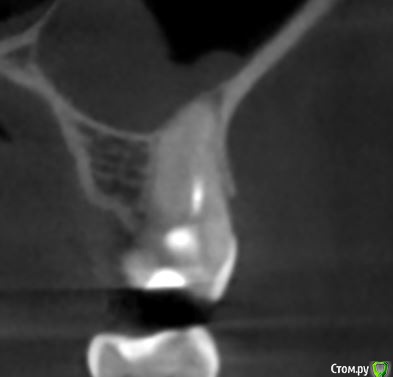

dmitrib81 Опубликовано 19 февраля, 2020 Поделиться Опубликовано 19 февраля, 2020 Помогите определить источник боли в зубе Ссылка на комментарий

krokomot Опубликовано 19 февраля, 2020 Поделиться Опубликовано 19 февраля, 2020 в медиальном корне недопломбировка и наличие вероятно 4ого канала. Ссылка на комментарий

dmitrib81 Опубликовано 20 февраля, 2020 Автор Поделиться Опубликовано 20 февраля, 2020 Зуб делали много лет назад. Примерно неделю назад появились периодические боли, бывает целый день не болит, потом снова ноющая боль. С приёмом пищи никак не связано. На горячие и холод реакции нетПодскажите, может ещё прислать фоток из КТ Пикассо, а то я в этом ничего не понимаю, просто разных фото экрана прислал, без какого-либо понимания, на что смотреть.. Ссылка на комментарий